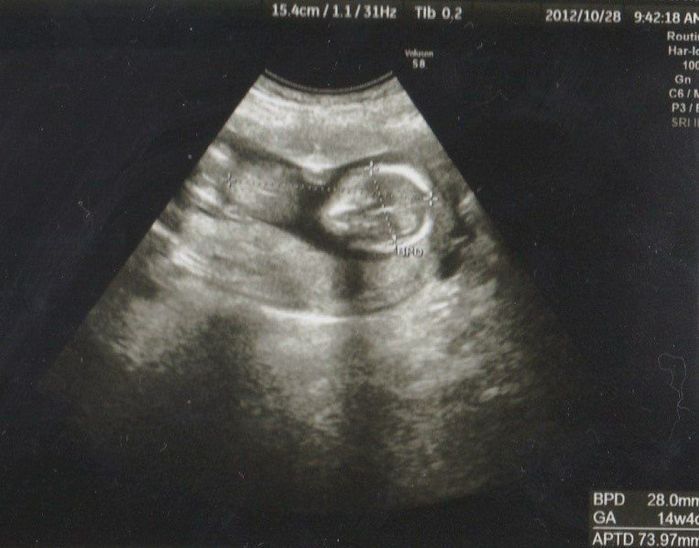

妊娠14週目のエコー写真

頭からお尻までの大きさが73.97mmにまで成長しました。右側に頭部、どちらを向いているかはわかりませんが、左側の丸っぽいのが脚に見えます。この週から経腹エコーだったので、長女も一緒に診察室に入ってエコー画像を見ることができました。緊張気味の長女もおなかに機械を当てて映し出される画像に目が点でした。